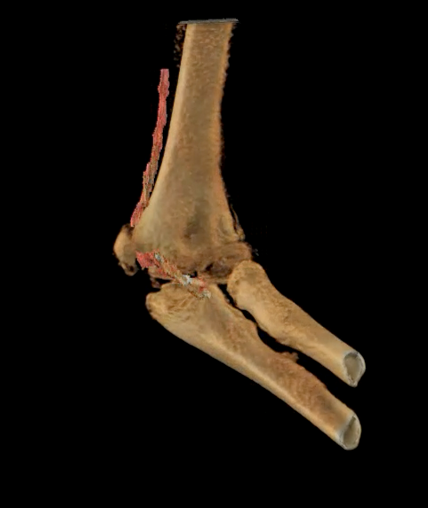

Median Nerve Entrapment at Medial Epicondylar Fracture Site of Elbow

Median Nerve Entrapment at Medial Epicondylar Fracture Site of Elbow. Intraoperative photo courtesy of Peter Fabricant, MD

3D visualization of bone (beige) and entrapped medium nerve (red) at the epicondylar fracture site of the elbow

3D visualization of bone (beige) and entrapped medium nerve (red) at the epicondylar fracture site of the elbow.